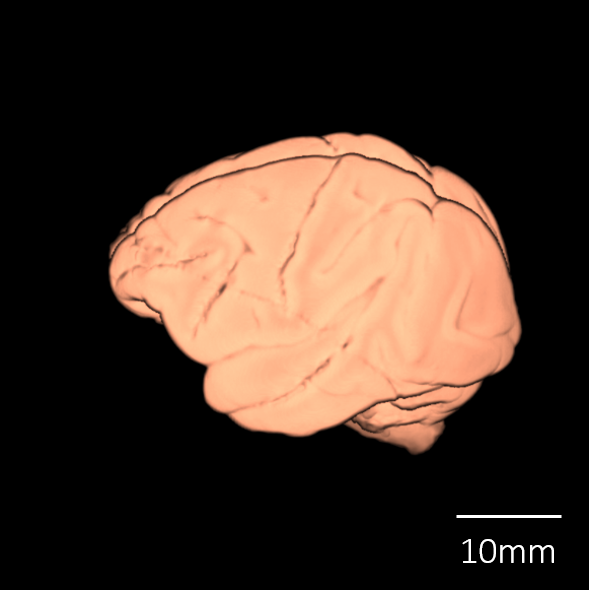

脳標本画像 Brain MRI Images

| 脳表再構成画像 |

![]() |